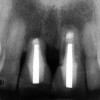

Figure 12  At 6 months postinsertion, the papilla receded as bone was lost.

Figure 12

Figure 13  Twelve months after placement, soft tissue migrated apically as bone between the implants continued to resorb.

Figure 13